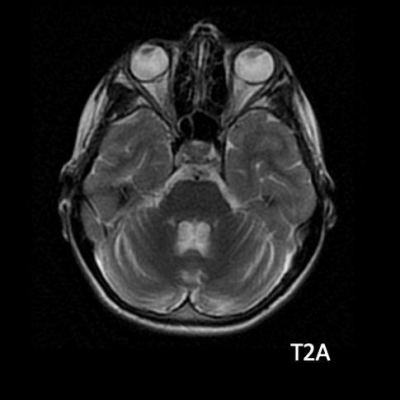

- B) Aksiyel T1A görüntülerde her iki lentiform ve kaudat nukleuslarda, talamuslarda simetrik hiperintensite (oklar) izleniyor. Bu düzeyde tariflenen sinyallerin SWI ve faz görüntülerde kalsifikasyon ile uyumlu olduğu görülmektedir (oklar). T2A görüntüde yaş ile uyumsuz serebellar atrofi ile uyumlu foliada derinleşme ve 4. ventrikül genişliğinde artış izlenmektedir (oklar).

- MRG’de akut fazda T2/FLAIR hiperintensiteyle birlikte giral şişme ile karakterize enfarkt-benzeri lezyonlar ve subkortikal beyaz cevher tutulumu görülür. DWI’da artmış sinyal dikkat çekmekle birlikte ADC değerlerinin normal ya da hafif artmış olması, baskın sürecin vazojenik ödem olduğunu gösterir.